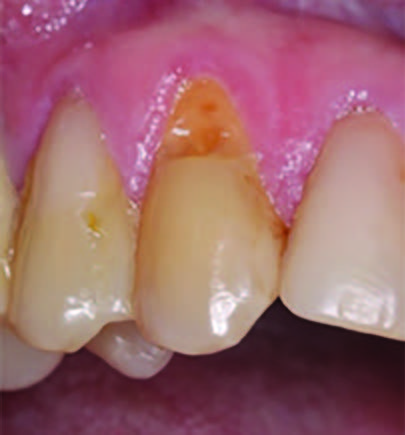

Figure 1.

Initial presentation of tooth #6 showing the Class V lesion with dislodged previous restoration and exposed dentin.